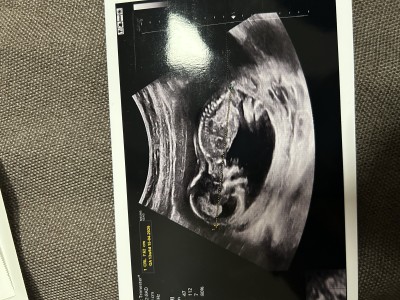

Ultrason kâğıdından anlayan var mı acaba rica etsem yorumlar mısınız

Gebelik haftası 13+6

Cinsiyeti erkek hayırlı olsun ben öyle gördüm

Çok teşekkür Allah razı olsun 11 haftalıkken tahminim erkek dedi bugün kontrolüm vardı yüzüstü durduğu için net göremedi bacak arasında bişey göremiyorum kıza benziyor 18. Haftada kontrol ederiz belli olur dedi

Benim oğlumda 11 haftalıkken bu şekilde şimdi 27 haftalıgız hep erkek dedi doktor sizinde erkek hayırlı olsun